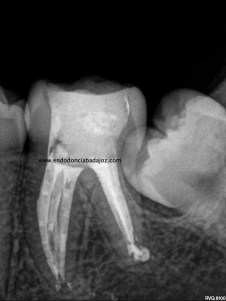

Como todos sabemos, encontrarnos dos conductos en la raíz mesiovestibular de un primer molar superior, cada vez es más frecuente, no por que antes no existiesen, sino por que cada vez somos más conscientes de su existencia,de la anatomía del sistema de conductos tan complicada que puede alojarse en esta raíz, con lo que buscamos ese cuarto conducto. Partamos de la base , que si los buscamos podremos localizarlos, pero hay veces que la cosa se pone algo más complicado, cuando, podemos apreciar un conducto más, quizás se trate de un istmo prolongado del cuarto conducto, pero que en cualquier caso debemos desbridar , limpiar y obturar, con lo que debemos tratarlo como otro conducto.

( Otra molar superior con 3 conductos mesiales)